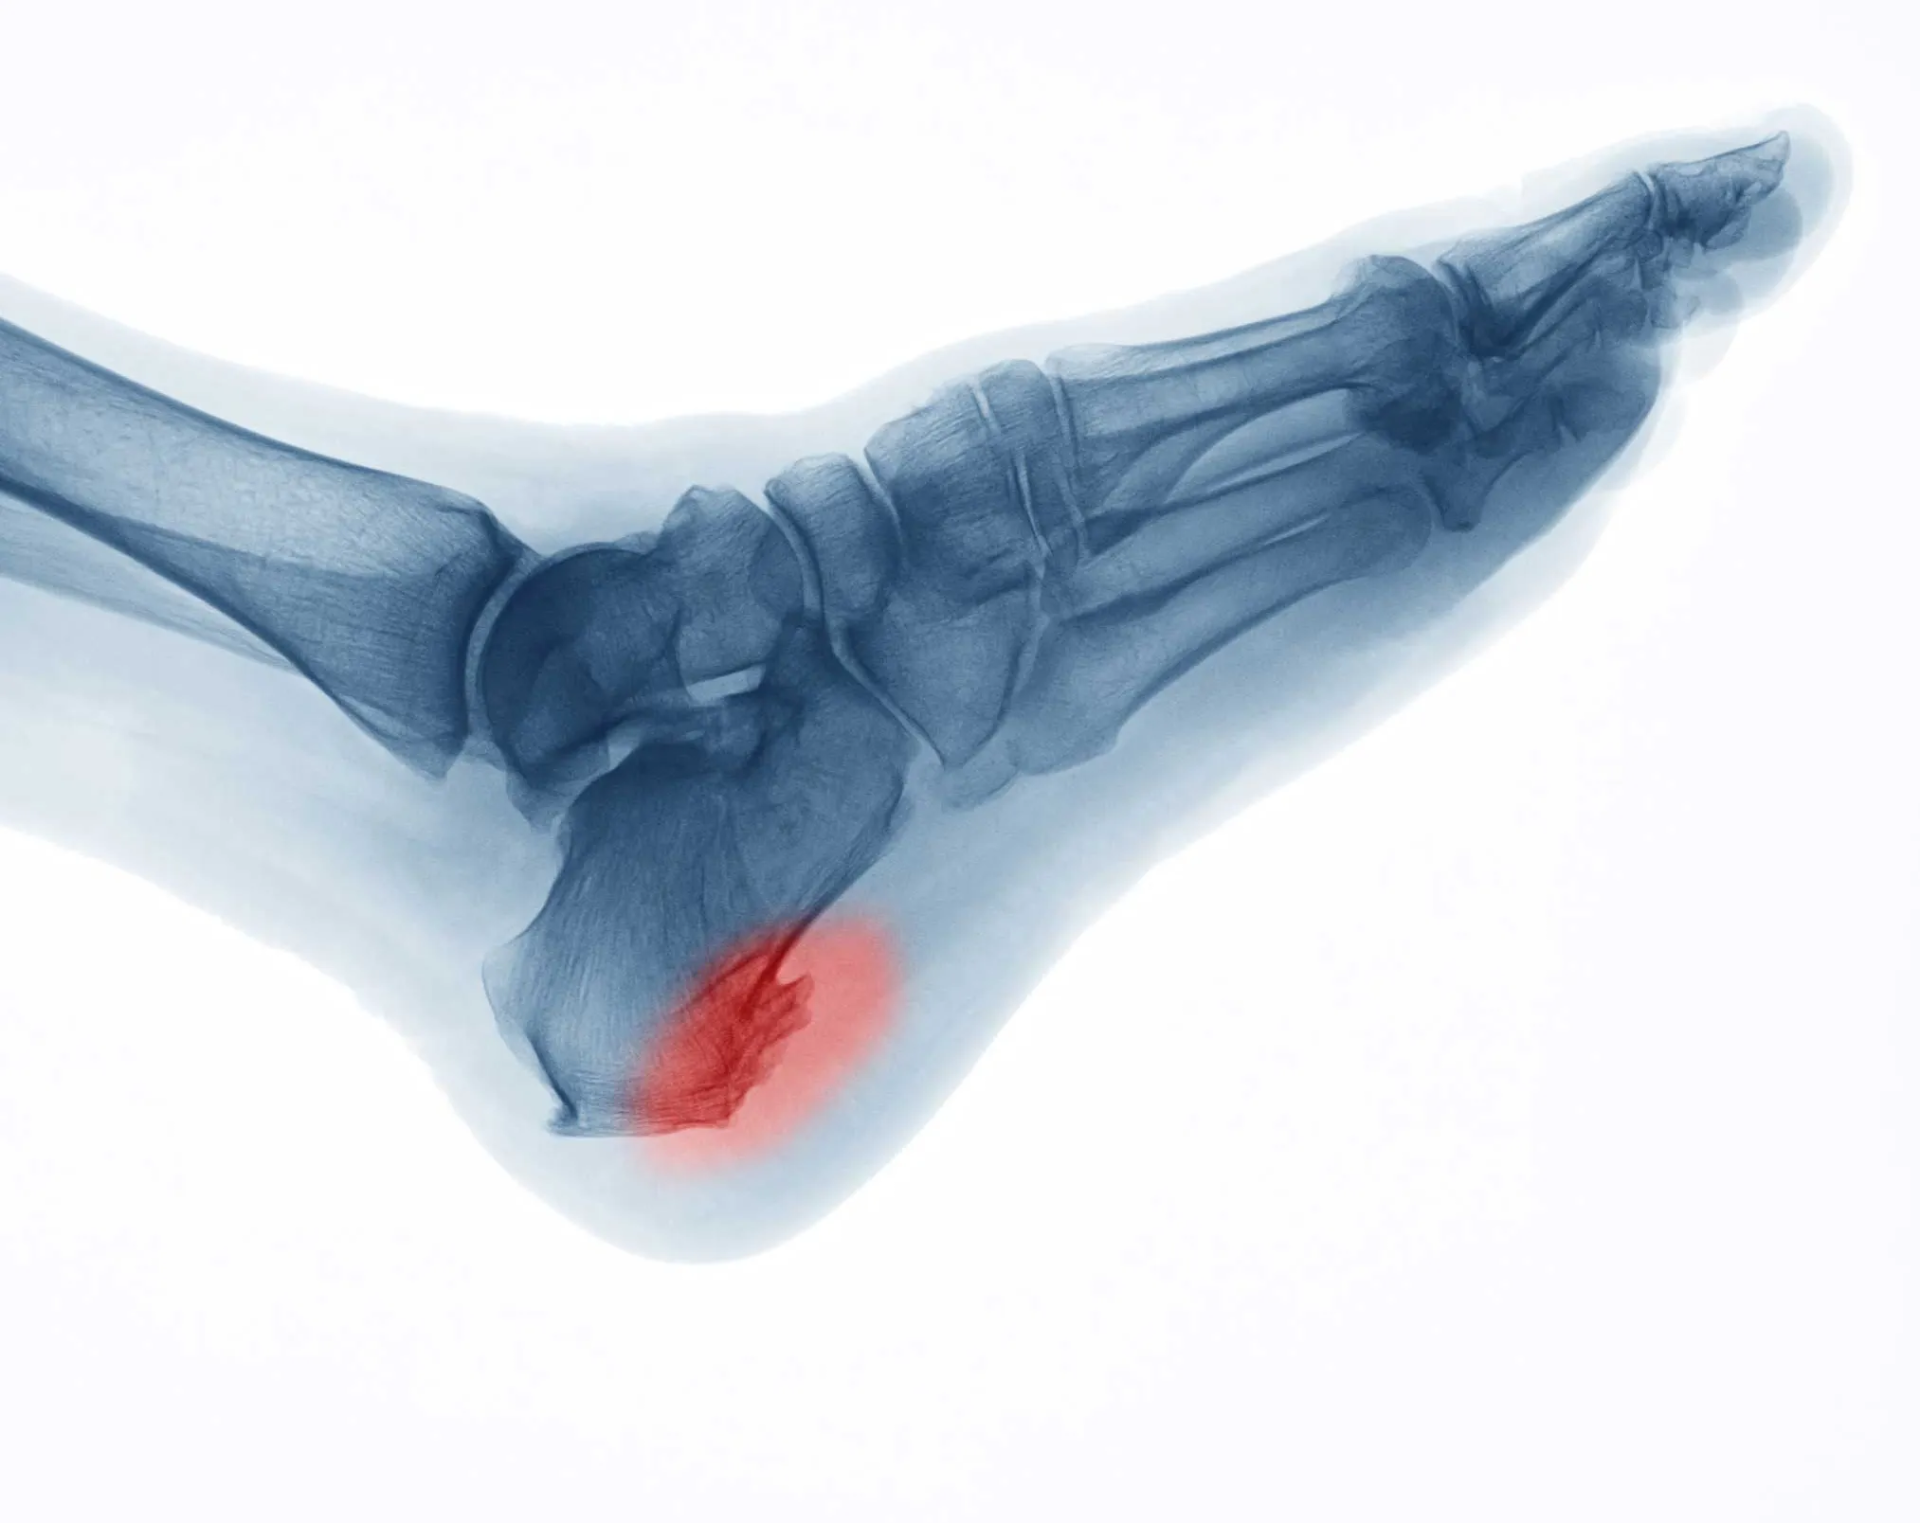

El espolón calcáneo es un crecimiento óseo, una pequeña calcificación en forma de lanza que aparece en el hueso del talón (el calcáneo).

El espolón calcáneo (o espolon calcareo, como a veces se busca) es un crecimiento óseo, una pequeña calcificación puntiaguda que se forma en el hueso del talón, el calcáneo.